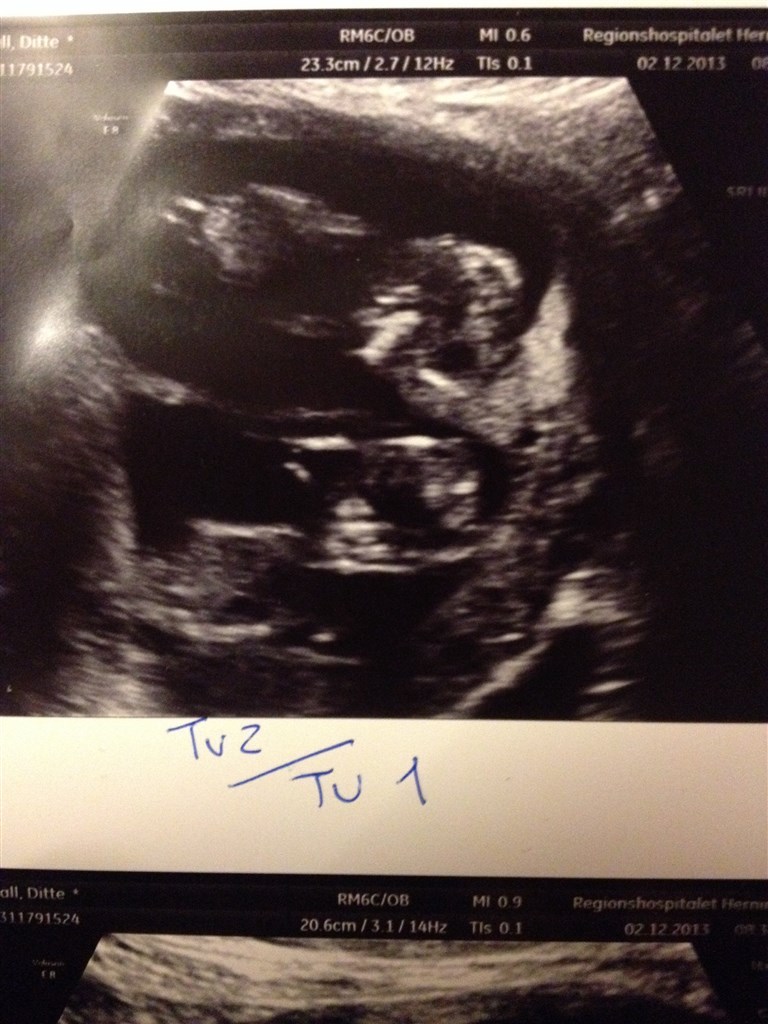

Så oprandt dagen for vores nf, de to troldeunger er bare helt perfekte

driller hinanden, vinker til far og mor og ligger med armene over hovedet. Alt i alt en helt fantastisk oplevelse

hun flyttede terminsdag en enkelt dag, fra den 10/6 til den 9/6.